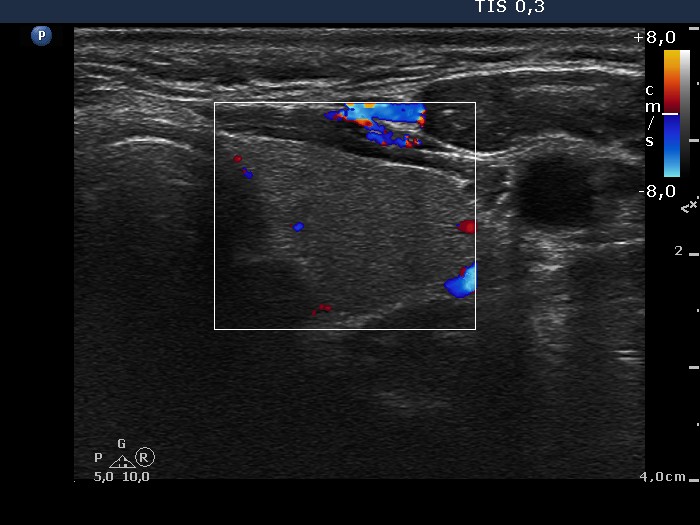

Thyroid cancers - case conp 015 (ultrasonographic picture 5)

Left lobe, transverse scan, color Doppler mode. The vascularization is not specific.